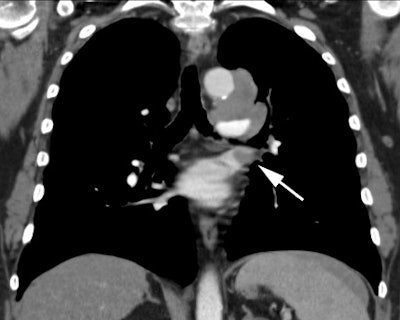

Example 2: This patient with non-small cell lung cancer demonstrates many findings which are suspicious for mediastinal invasion. There is greater than 3 cm of contact between the mass and the mediastinum, loss of the mediastinal fat plane between the mass and the left pulmonary artery, deformity of the left pulmonary artery, and pericardial thickening (yellow arrows). The patient also demonstrates contralateral mediastinal adenopathy (N3 nodes -- white arrow), subcarinal adenopathy (SC), and bilateral pleural effusions.